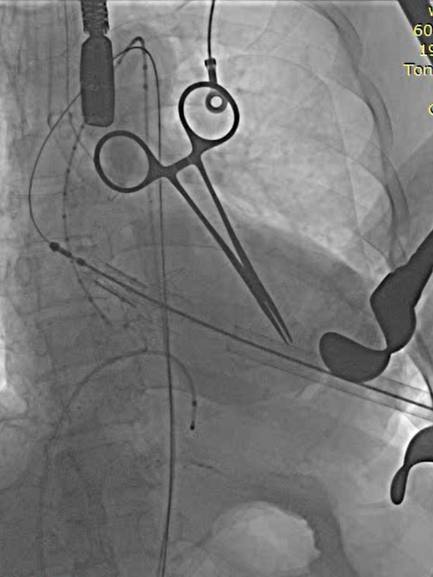

全麻后取仰卧位,消毒。取左前胸第5肋间切口进胸,腔镜辅助下游离左侧乳内动脉(LIMA)备用。肝素化。显露左前降支动脉(LAD),于其狭窄远段切开,将LIMA与之端侧吻合。血管桥排气后开放,测桥血流量满意。经股静脉植入心脏临时起搏器并确认正常工作。经股动脉置入造影导管至升主动脉根部,造影显示主动脉瓣大量反流,窦部结构可。3-0 Porlene线带毛毡片做荷包,经单弯导管引导超滑导丝至降主动脉,更换加硬导丝,导丝尖端于髂动脉分叉处。置入带主动脉瓣输送系统,造影定位下,准确释放29# J-Valve至主动脉瓣瓣环处,造影显示左右冠脉血流正常,TEE证实瓣膜位置可,未见明显反流。撤出输送系统,收紧荷包并缝合止血。放置胸管,逐层关闭各切口。

释放瓣膜,撤离输送系统

DSA显示无瓣周漏